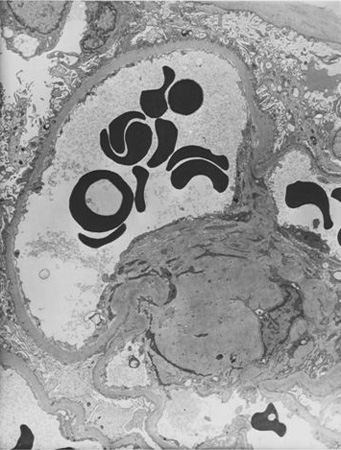

Doença renal diabética

Doença renal diabética: na posição de 5 horas - nódulo de Kimmelstiel-Wilson no início, um aumento arredondado na matriz mesangial que provavelmente foi originado em relação a um microaneurisma

Do acervo do Dr. Raoul Fresco; usado com permissão